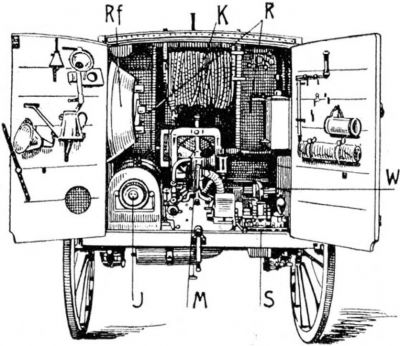

Takhle ta vozidla vypadala v průřezu:

To je pravda, ale nevlezly se do náklaďáčku ani velikostí, ani hmotností. M. Curie navrhla takové uspořádání, vč. karoserie, že to bylo použitelné. Takže první tuning v dějináchWolf píše:Röengenove prístroje boli tiež používane na kontrolu tovaru. 15.2.1915 bol v New Yorku zachytený kontraband gumy ukrytý v balíkoch tovaru, ktoré mali byť prepašované do Nemecka. Prístroj obsluhoval Richard Muller z Columbia University.

A kromě toho, my se bavíme o přístroji jednak humanitárním (žádné vybírání cla, pomoc raněným) a jednak sestrojeným tak, aby byl sériový, a vydržel převážení po cestách - necestách rozrytých dělostřeleckou palbou. Vlastně byly novinkou už i ty auta, schopná provozu v terénu...

Našiel som obrázok s popisom, podľa ktorého by sa malo jednať o koňom tahaný voz s roengenovým vybavením používaný Nemeckou armádouRase píše:díky všem za rozšíření zajímavých informací. Chtěl jsem se ale zeptat, používaly se rentgeny, nebo ony radonové injekce, i na druhé straně fronty ?

Podľa tohto zdroja (http://www.wehrmed.de/article/2590-neue ... ieges.html) mali Nemci na začiatku vojny iba 12 mobilných röntgenových vozidiel. V priebehu septembra 1914 zaobstarali ďalších 20 zariadení (mobilných a poľných- statických). Na začiatku vojny pripadal jeden prístroj na cca 65 000 nemeckých vojakov. V auguste 1918 mali nemci už viac ako 270 zaradení, čo je jedno na cca 40 000 vojakov. Z toho 35 mobilných a 16 statických prístrojov bolo koristných.